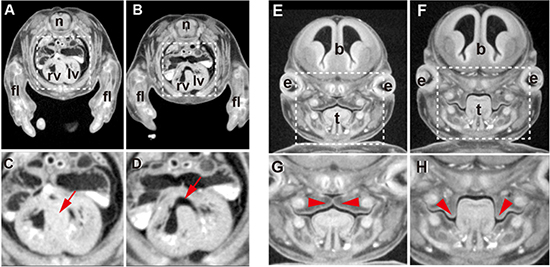

図3 micro-CTイメージングによる表現型解析の一例

A-D: 胸部心臓付近横断面像。A、Cは正常個体、 B、Dは変異体。C、Dは、それぞれA、B内点線四角領域の拡大図。正常個体では、右心室(rv)と左心室(lv)は心室中隔(C図内赤矢印)で隔てられている。変異体心臓では、心室中隔の形成が不十分(D図内赤矢印)で心室中隔欠損の症状を示す。その結果、動脈血と静脈血が分離できない。

E-H: 頭部・顔面部分冠状断面像。E、Gは正常個体、F、Hは変異体。G、Hは、それぞれE、F内点線四角領域の拡大図。正常発生では、鼻腔と口腔は軟口蓋(G図内赤矢頭)で分離される。 変異体では、軟口蓋形成が不全(H図内赤矢頭)で、軟口蓋裂の症状を示す。 Nは神経管、flは前肢、lvは左心室、rvは右心室、bは脳、eは眼球、tは舌を示している。